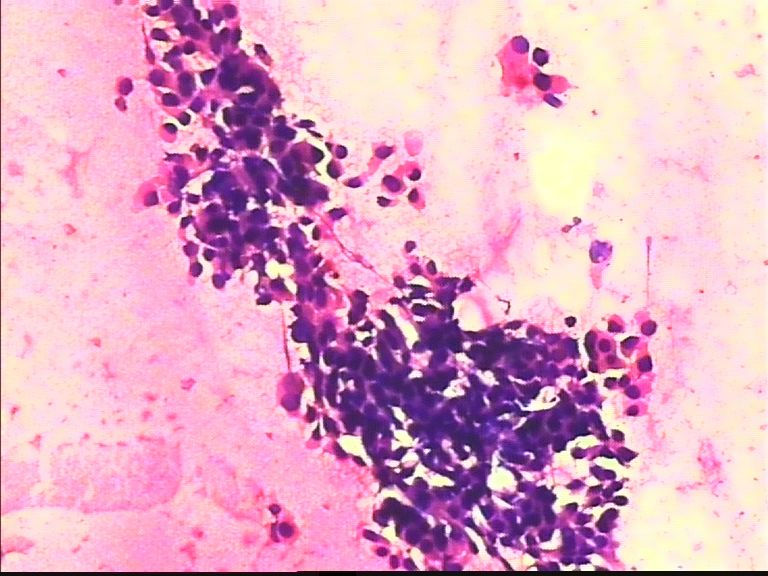

38岁 乳腺肿瘤 女

• 38岁 乳腺肿瘤 女图2

图2

乳腺癌

乳腺癌。

浸润导管癌

好像重复了。浸润性导管 癌。

从所给图看恶性是没什么问题!染色有点过,染色质结构欠清晰;关于细胞学判断浸润的问题我想应综合来判断,如单个细胞的异形性,细胞整体弥散情况,细胞微粒结构以及间质成分等等,个人的认识也起到一定因素,细针穿刺中最常规用的还是--导管癌。